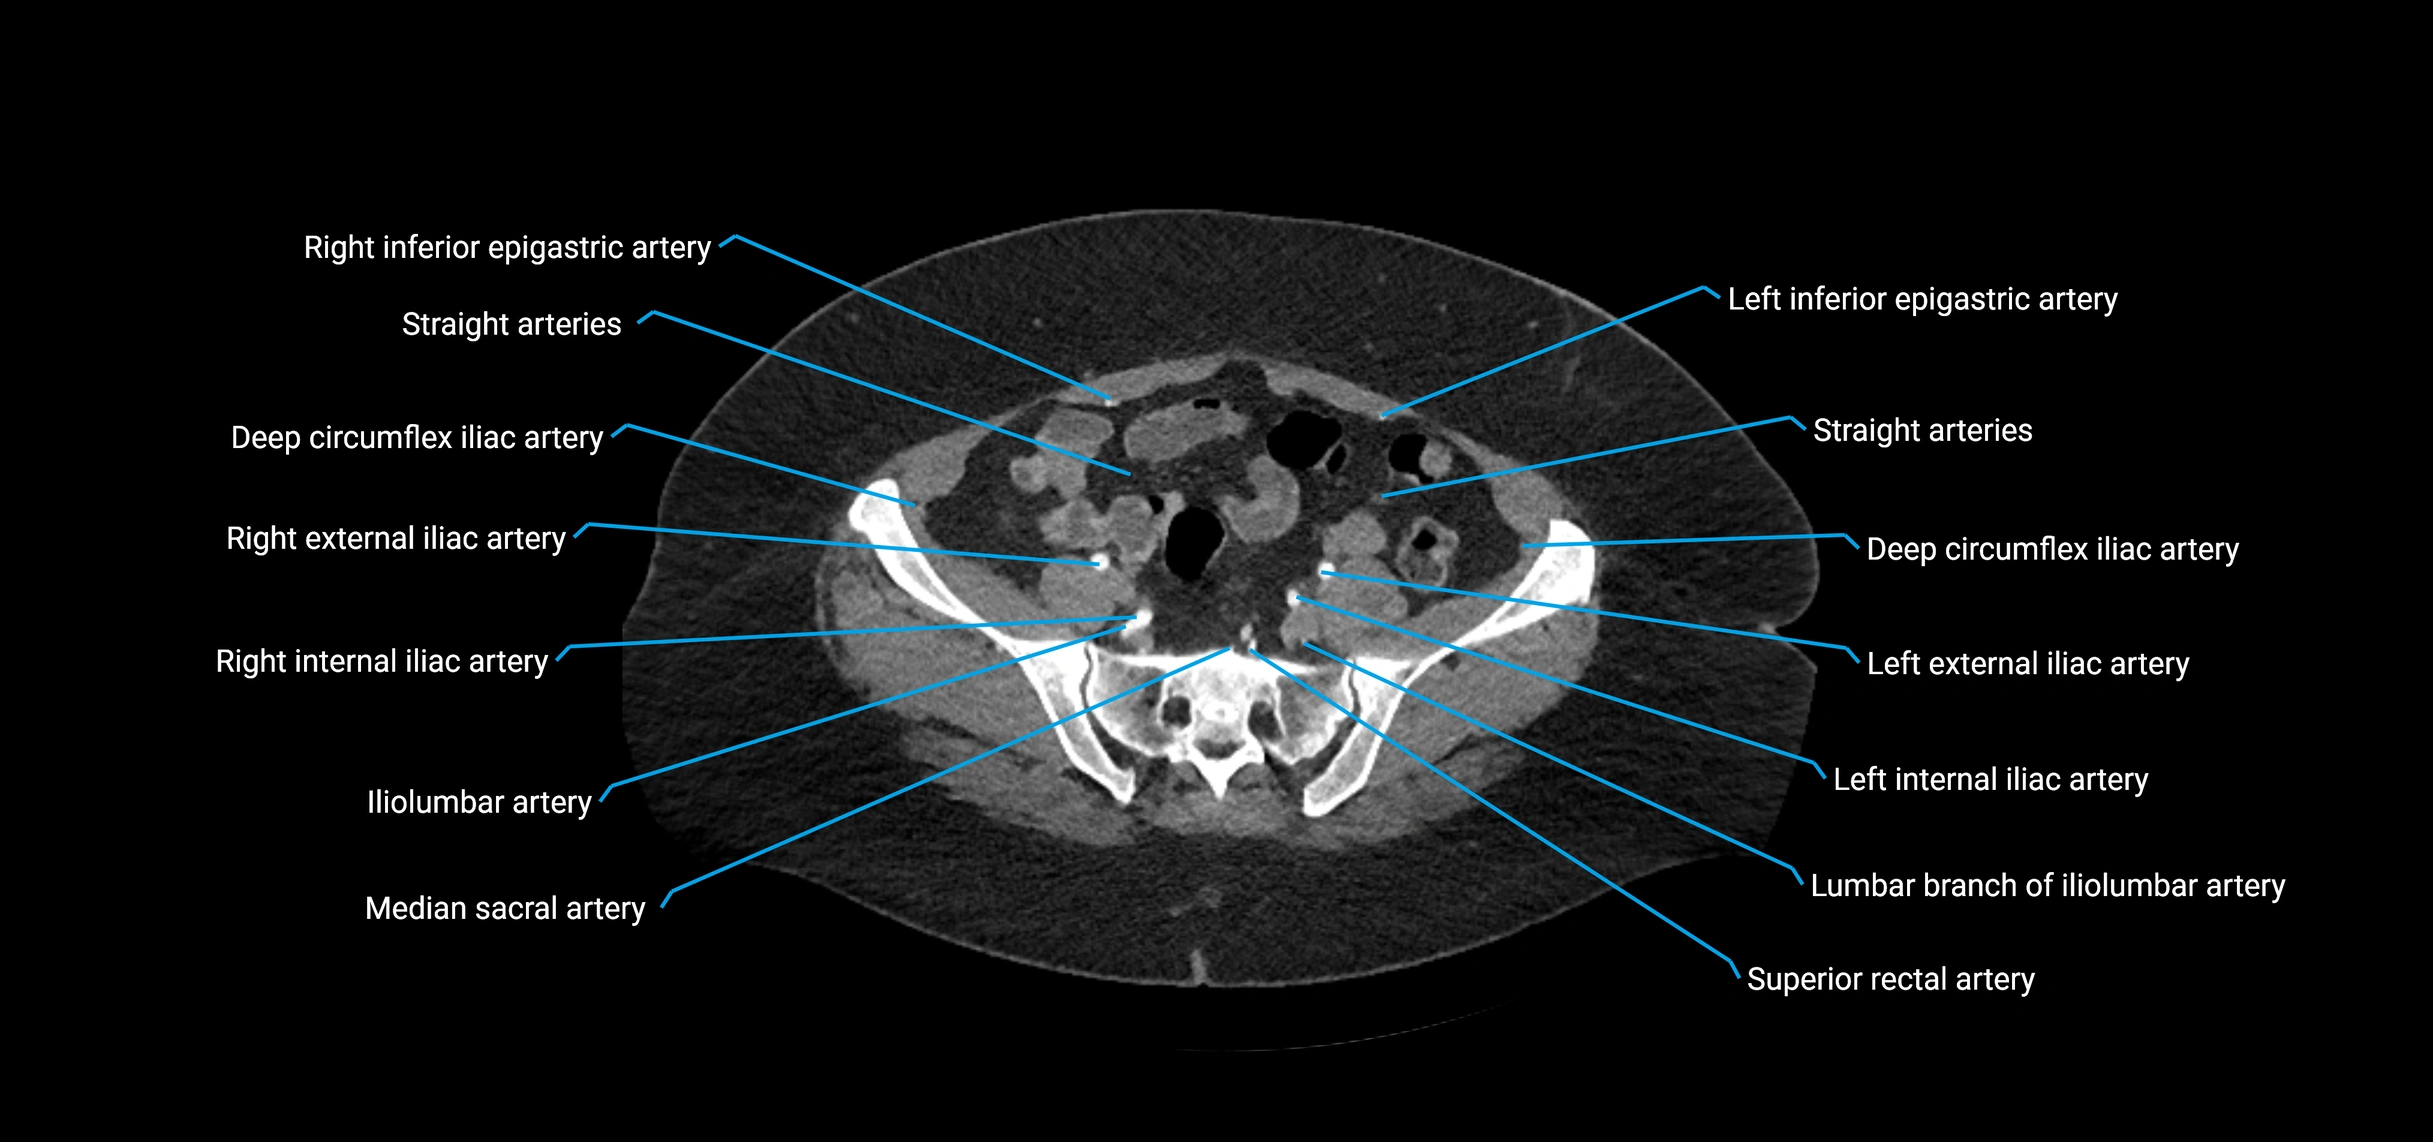

Contrast-enhanced CT (CTA):

• Gold standard for abdominal aortic imaging

• Provides excellent detail of lumen, wall, aneurysm, thrombus, and branch vessels

• Multiplanar and 3D reconstructions help in aneurysm measurement, stent graft planning, and dissection evaluation

• Detects acute rupture, traumatic injury, or occlusion with high sensitivity